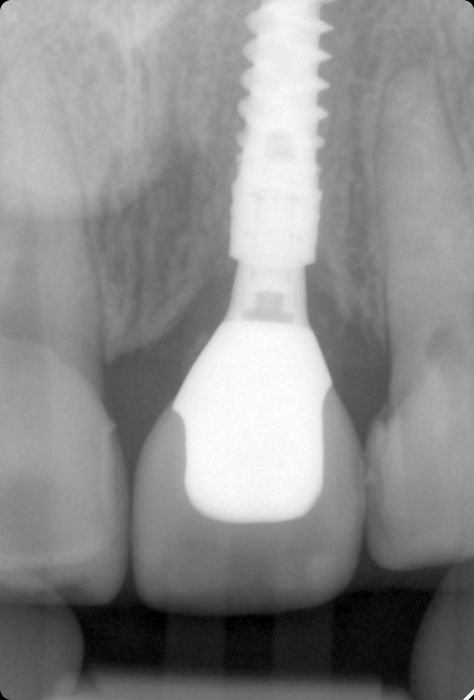

To eliminate any inflammatory or infectious tissue that may have remained in the socket, the periapical region was carefully curetted, and extensive irrigation was performed with normal saline. The freehand and flapless surgery involved the immediate placement of a Straumann® BLX Implant ∅ 3.75 mm - Regular Base -SLActive® 12 mm Roxolid® in position #21 following the manufacturer's instructions to ensure primary stability (Figs. 16-20). The drilling was located on the center of the extraction socket in the palatal wall, and the implant site was to the palatal side in a prosthetic-driven position.

The patient is recalled for prophylaxis and follow-up every year. After three years, the clinical and radiographic outcomes show good esthetics, osseointegration, and maintenance of peri-implant tissues. The patient was delighted with the esthetic and functional result and presented no mechanical or biological complications (Figs. 41,42).